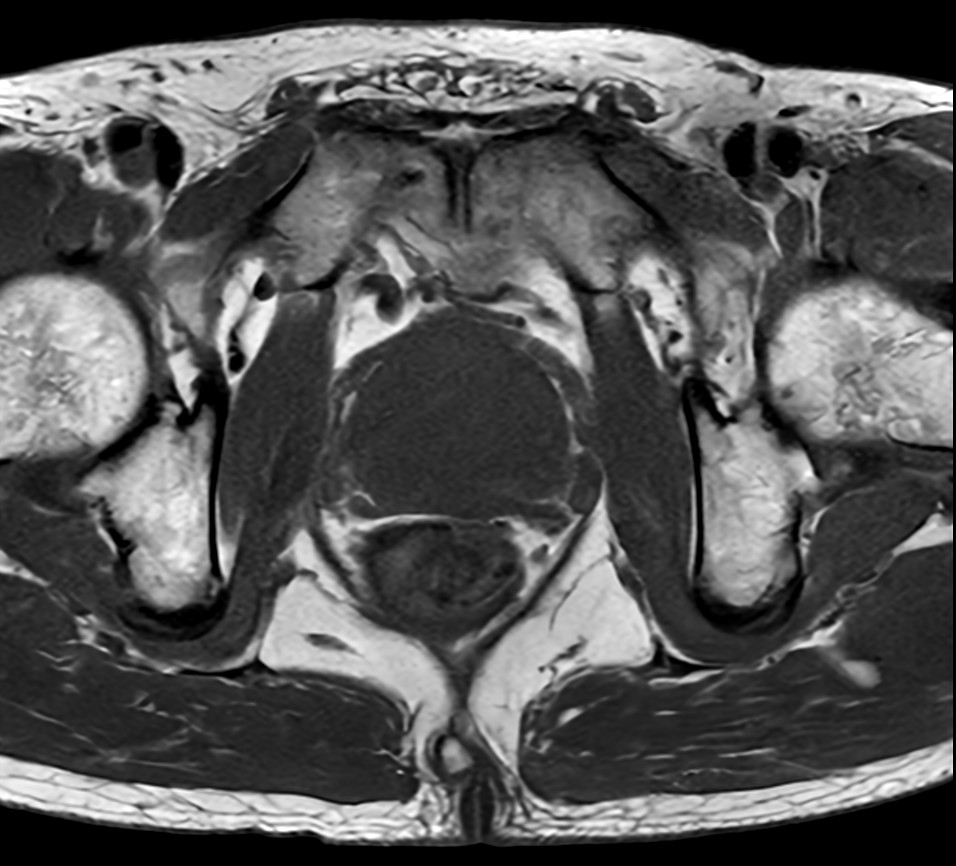

Fast Prostate imaging with SmartSpeed Precise

Kumamoto Chuo Hospital Japan

Used Solution